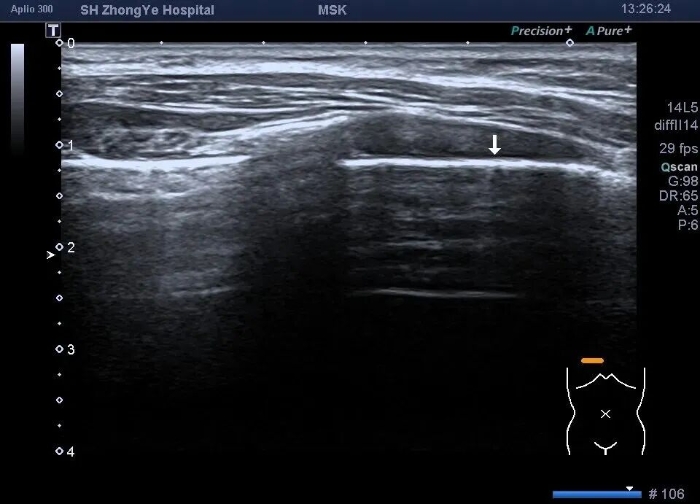

正常肺: 肺泡充满气体,气/液比极高,超声仅显示胸膜线及A线(水平混响伪像),无法穿透。

A线: 水平排列的平行线,这是我们希望看到的,绝大部分代表正常的、充满气体的健康肺 。